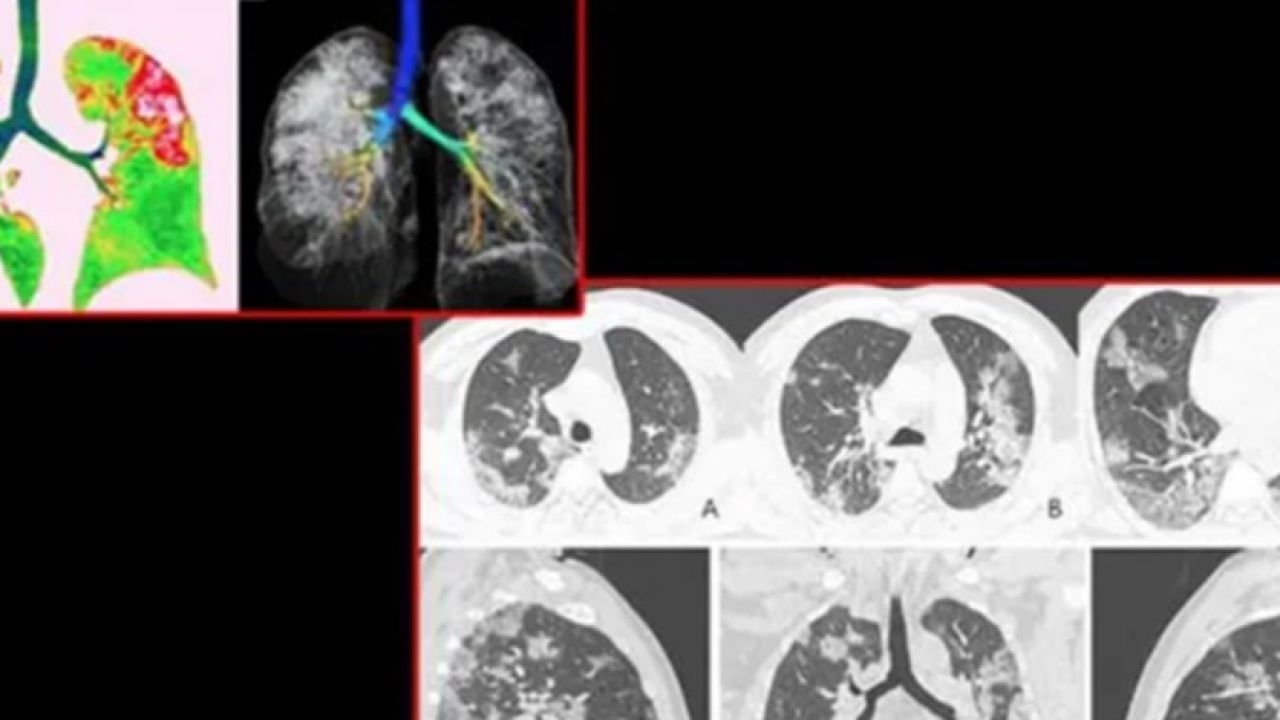

İngiliz tabloid gazetesi Daily Mail'deki haberde; Wuhan'a gittikten sonra hastalanan 54 yaşındaki bir kadının ciğer röntgenleri paylaşıldı. Hastanın yüksek ateş, öksürük, halsizlik ve göğüs ağrısı şikayetiyle hastaneye gittiği belirtilirken, hastaya oksijen ve antibiyotik verildiği belirtildi. Japonya'ya döndükten sonra hastanın ilaç tedavisiyle birlikte iyileştiği açıklandı. Haberde, bu tür değişikliklerin SARS ve MERS hastalarında ki duruma benzediği belirtildi.